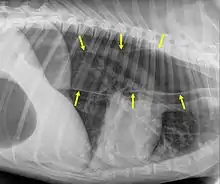

Megaesophagus, also known as esophageal dilatation, is a disorder of the esophagus in humans and other mammals, whereby the esophagus becomes abnormally enlarged. Megaesophagus may be caused by any disease which causes the muscles of the esophagus to fail to properly propel food and liquid from the mouth into the stomach (that is, a failure of peristalsis). Food can become lodged in the flaccid esophagus, where it may decay, be regurgitated, or may be inhaled into the lungs (leading to aspiration pneumonia).

An important distinction in recognizing megaesophagus is the difference between when a dog regurgitates or vomits. When a dog regurgitates there is usually not as much effort involved as when a dog vomits. Often when regurgitating, the dog will tip its head down and the liquid and/or food will almost appear to "spill out" of its throat.

One of the primary dangers to a dog with megaesophagus is aspiration pneumonia. Because the food stays lodged in the throat, it can often be inhaled into the lungs causing aspiration pneumonia. One way to avoid this is to make sure that every time the dog eats or drinks anything, that the dog sits for at least 10 minutes afterwards or is held in a sitting up or begging position. This disorder has a guarded prognosis, however a successful management technique is vertical feeding in a Bailey Chair.[5]